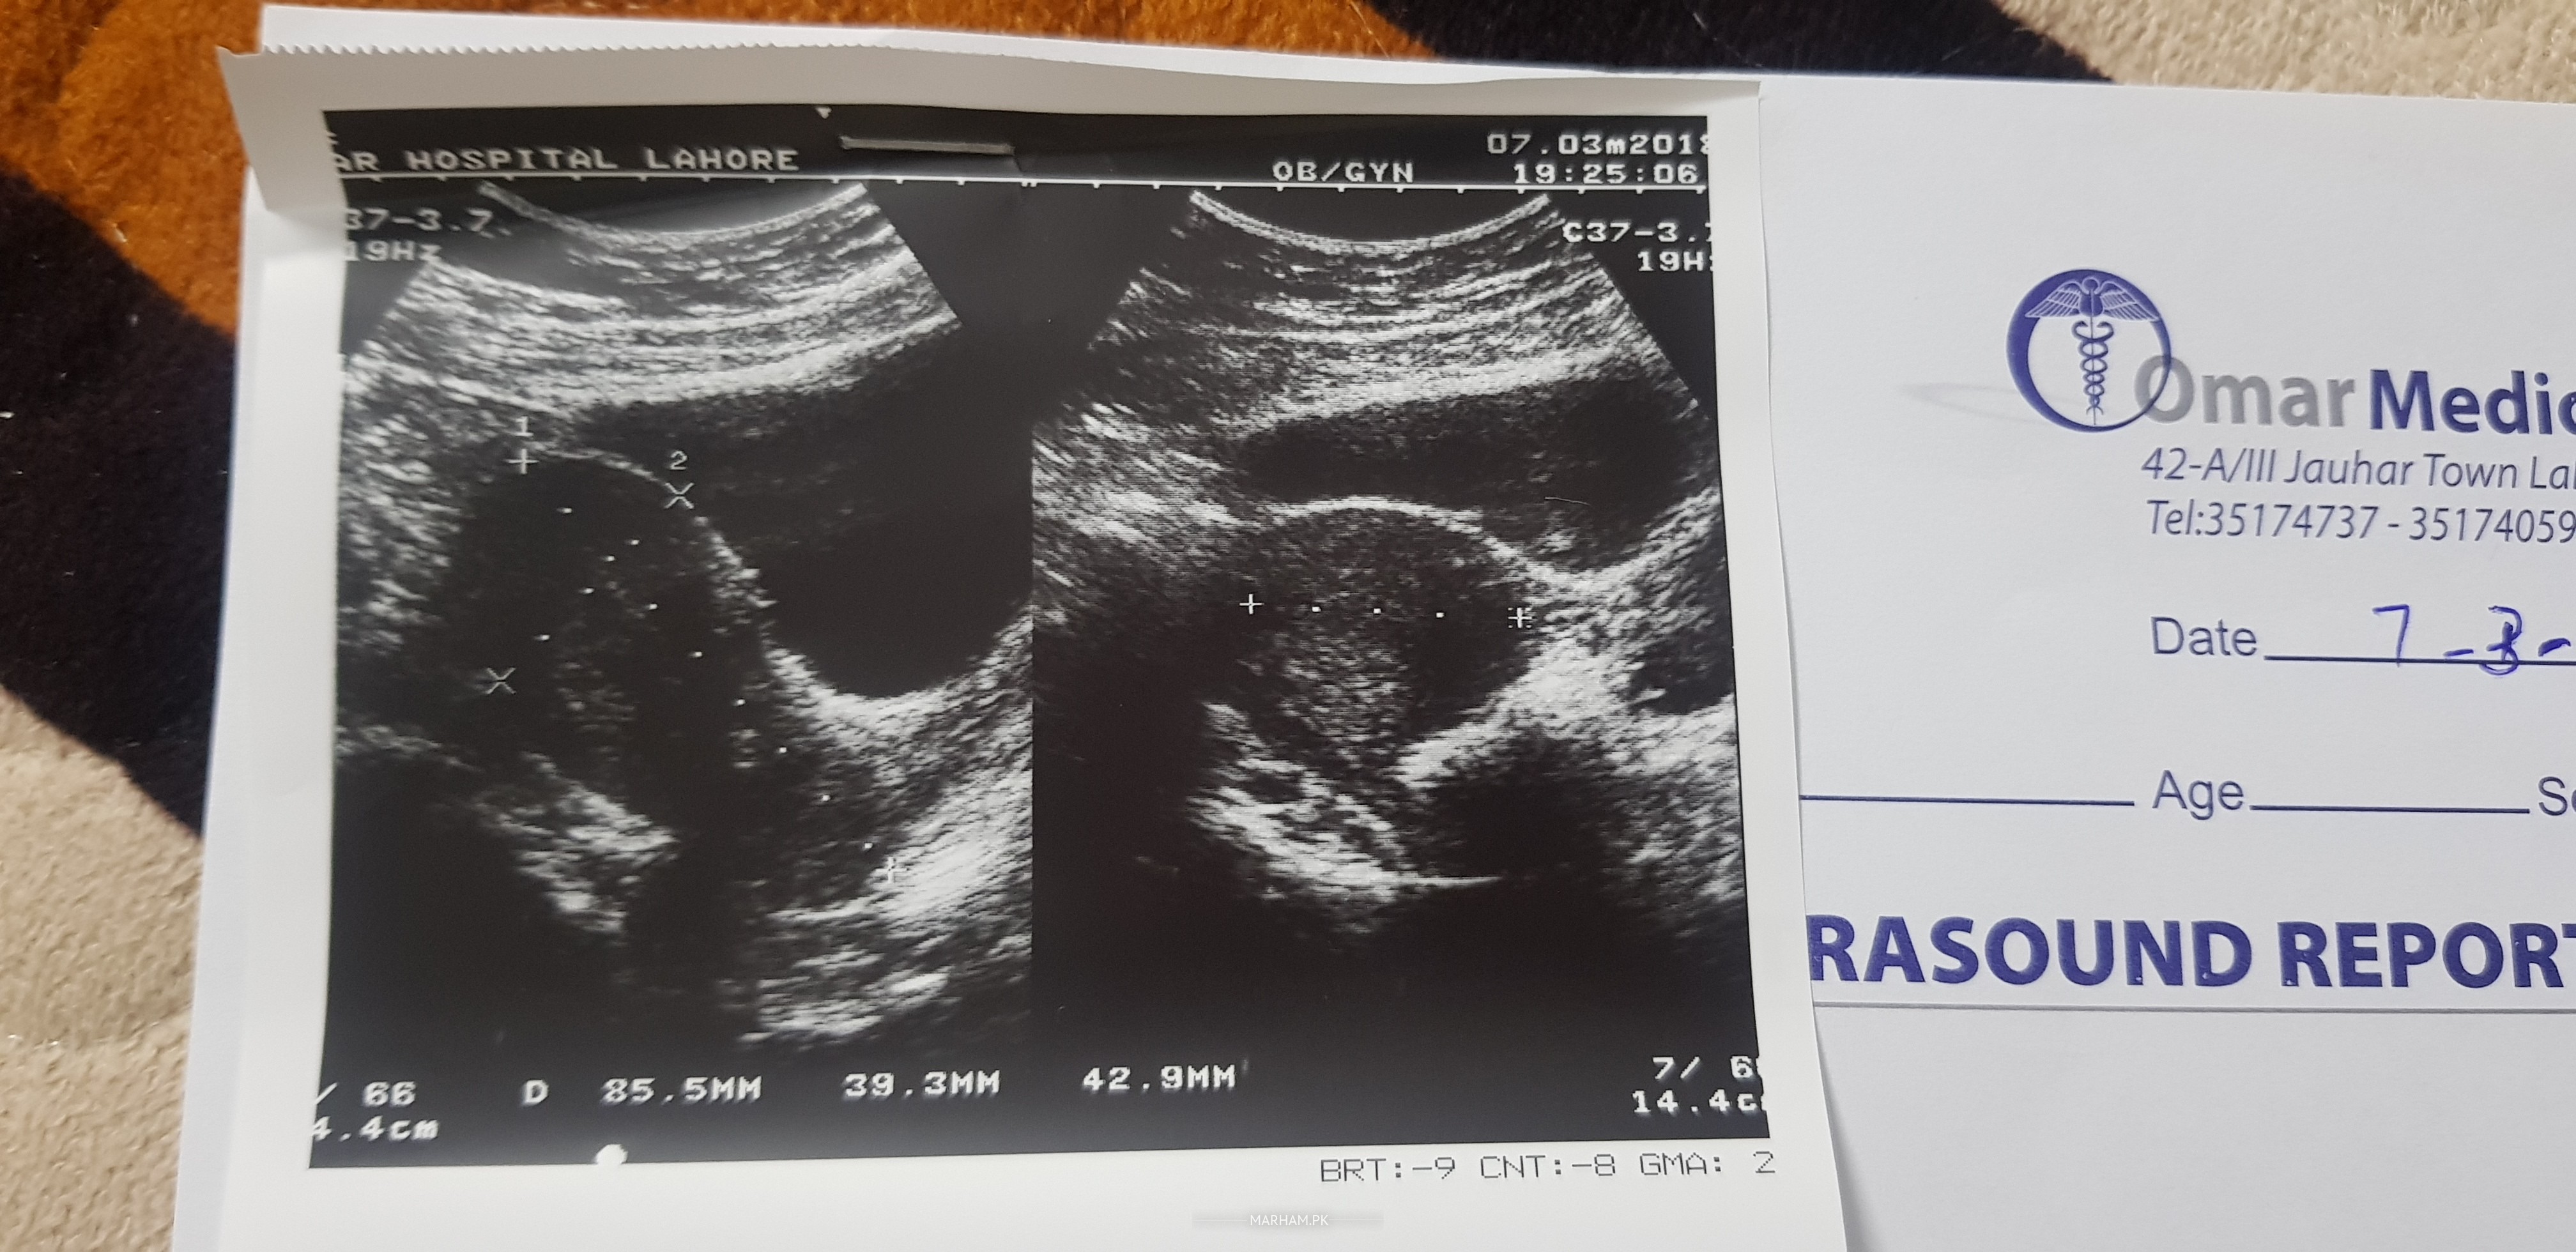

My period cycle was getting longer from 28 days to 35 days. Doc advised me to do hormonal test at 2nd day and ultrasound at 12th day of cycle respectively (reports are attached). tsh 2.29 lh 6.83 fsh 5.90 prolactin is 12.3 . i am married from 1 yr. Plus i am trying to conceive from last 2 months. She prescribed me metformin pregnol and adfolic tablets for 6 months. Now i want to know that should i get another opinion or should i continue with the medicines. Plus what is the issue specially with hormones. Bcz the doc was not in mood to tell me. Also she written on prescription no issue of pcos. plz confirm I shall b v thankful.